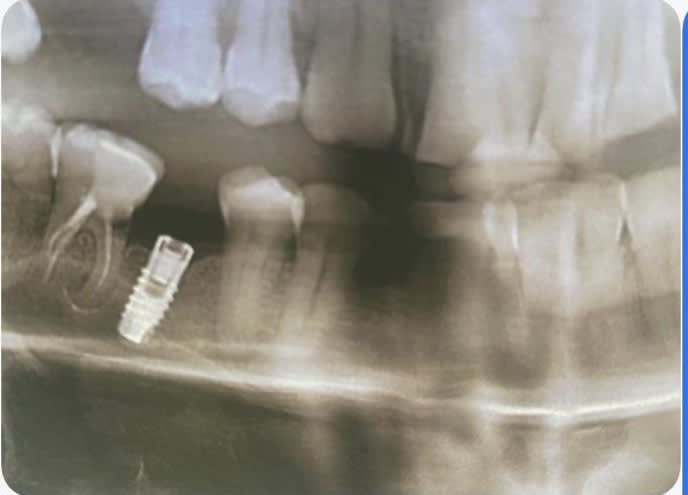

Bonjour, est-ce que quelqu’un peut me dire quelle est la marque de cet implant ? Merci d’avance

Rétro pour être certain à 100%

Mais amha c’est ça

https://whatimplantisthat.com/implants/details/endure-fixture-cp-old-threads

merci Pluton , je te fais suivre une rétro rapidement mais ça l'air de coller